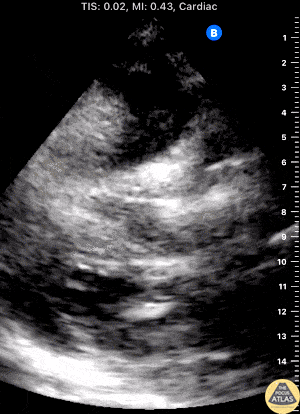

50s F found to be in cardiac arrest by EMS in the setting of 3 days hematemesis, achieved ROSC, and this image was seen on POCUS performed by EMS while packaging for transport. This subxiphoid view demonstrates the presence of organized cardiac activity with no large pericardial effusion, but free peritoneal fluid is seen adjacent to the liver, superficial to the diaphragm in this image, and the falciform ligament is also briefly seen. Zachary Hutchins South Metro Fire Rescue, Centennial, CO